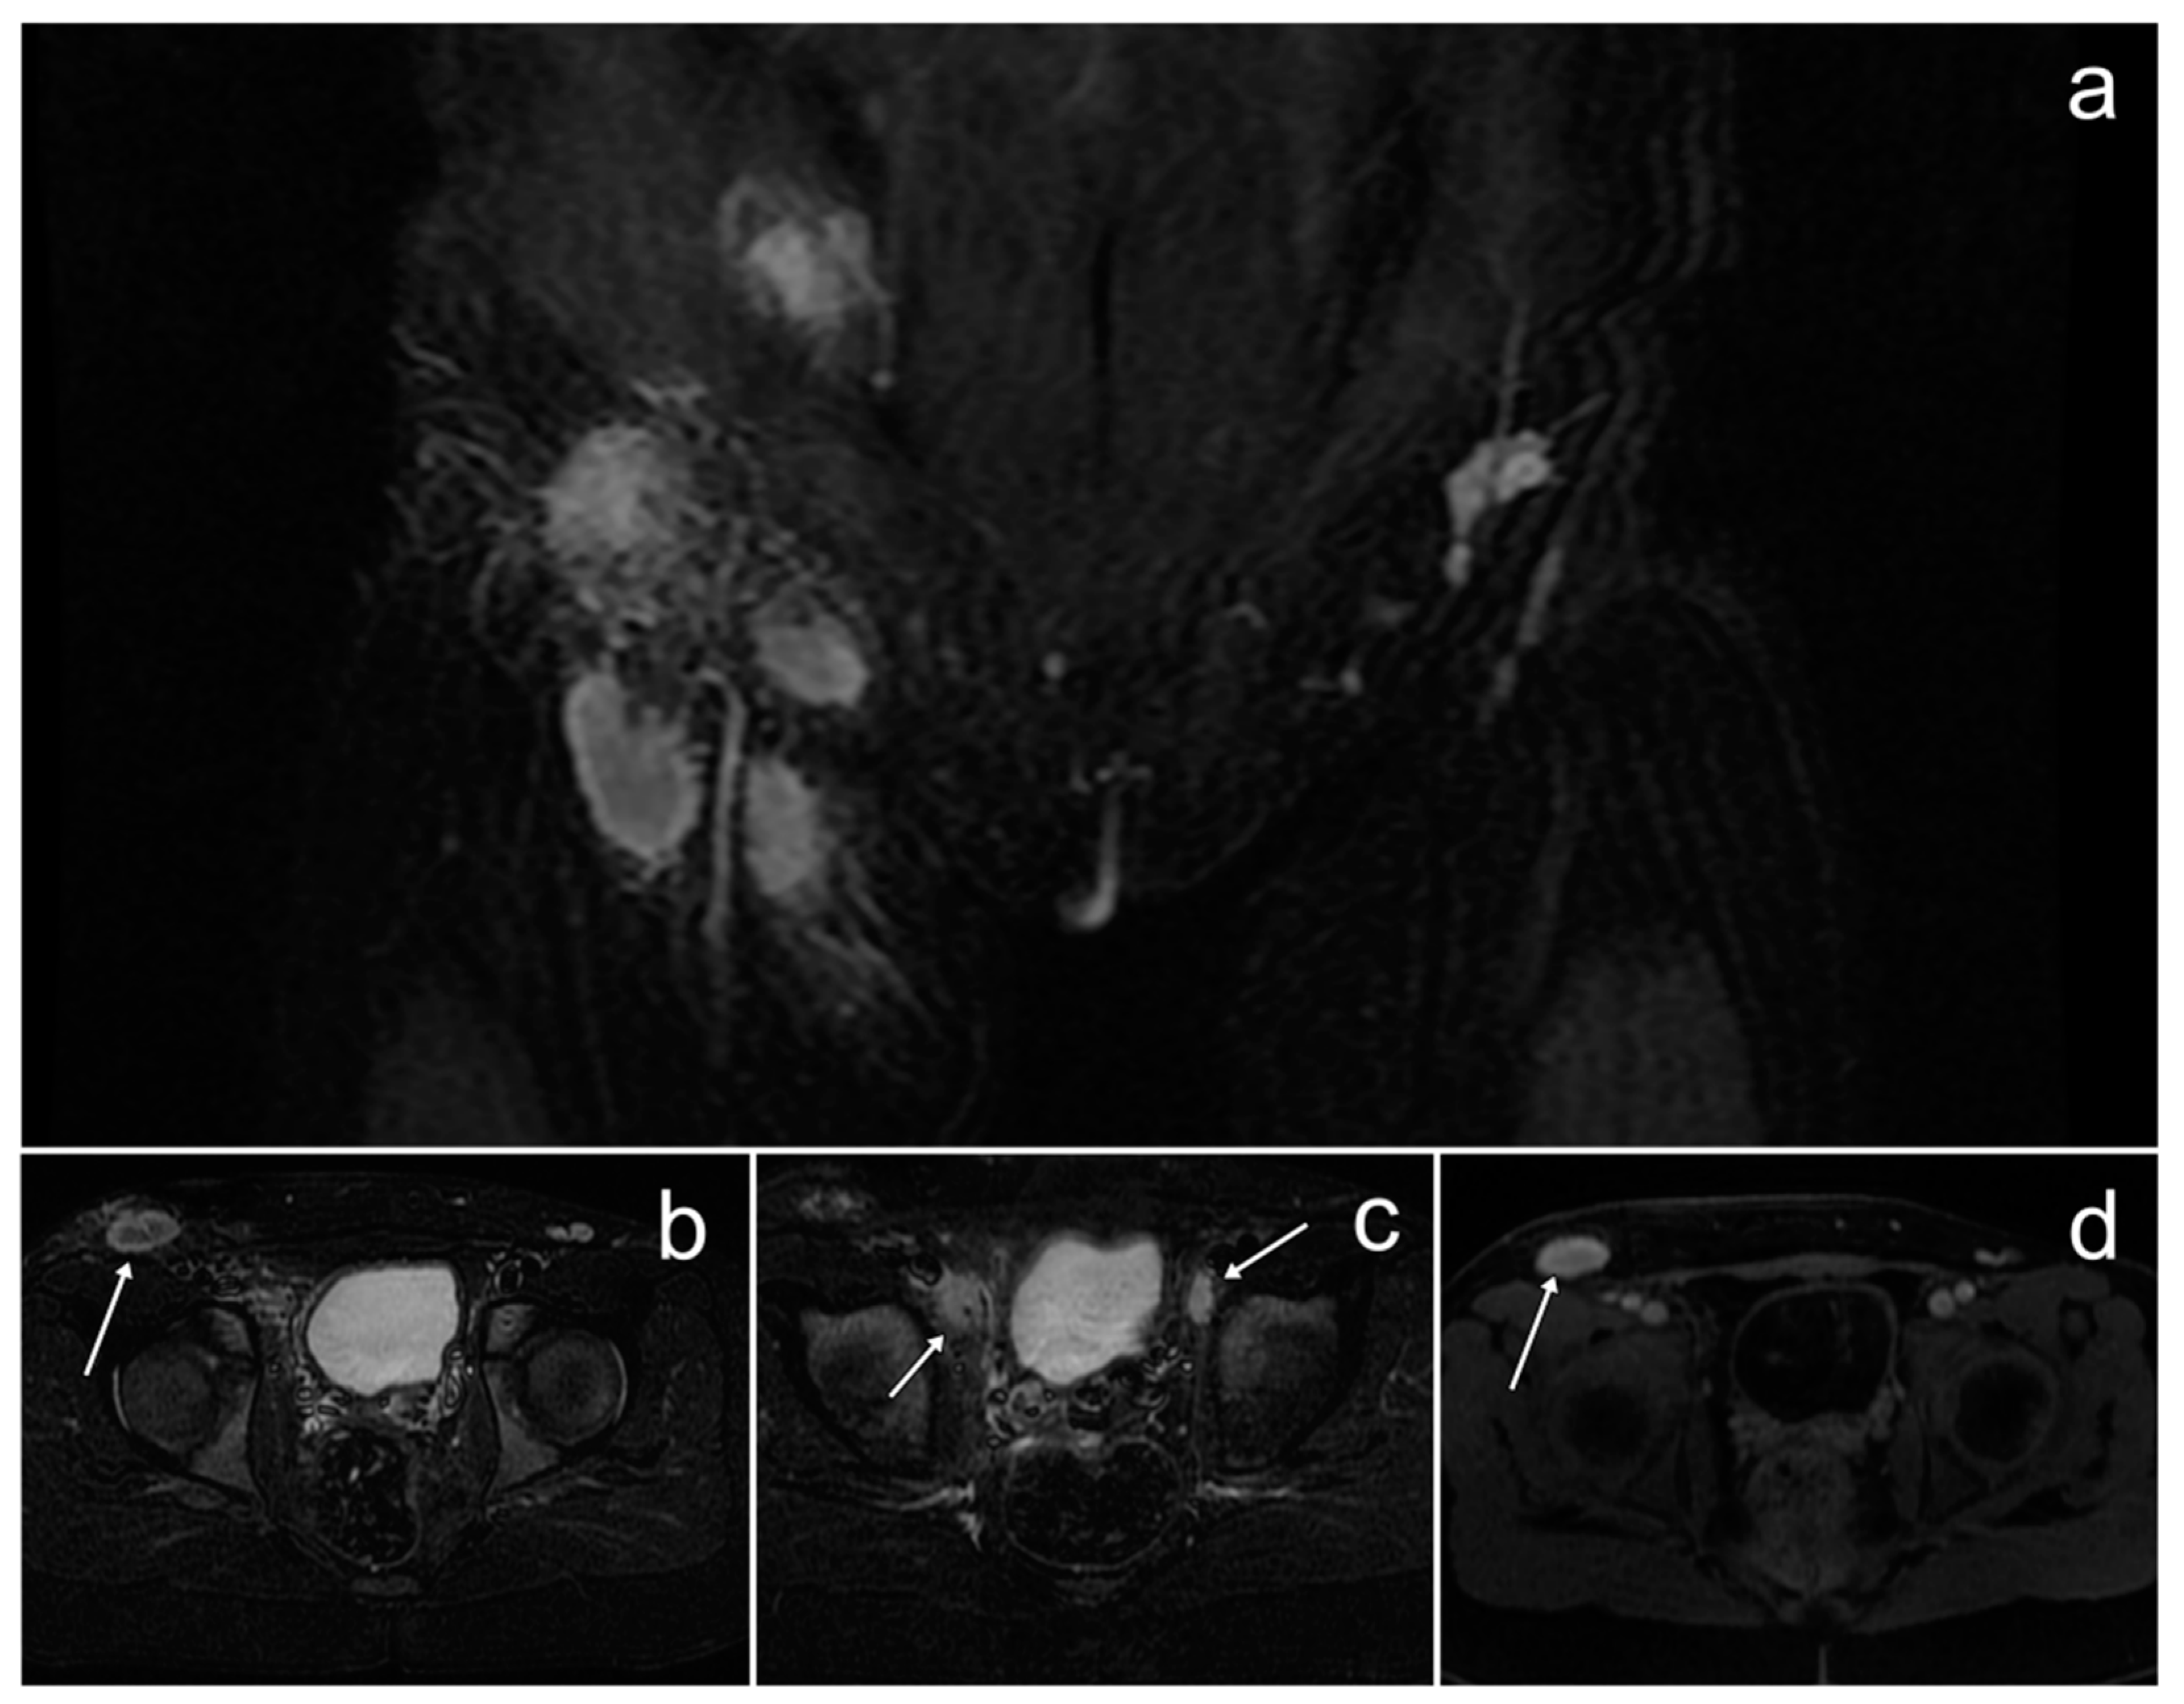

3.9. Rosai–Dorfman Disease Involving the Pelvic and Inguinal Lymph Nodes

Case Report

| Rosai–Dorfman disease involving the pelvic and inguinal lymph nodes | nodal form: significantly enlarged pelvic/inguinal lymph nodes; extranodal form: abnormal presacral mass; diffusion restriction; homogeneous contrast enhancement | - | palpable mass in subcutaneous tissue, fever, weight loss, night sweats, bone pain |